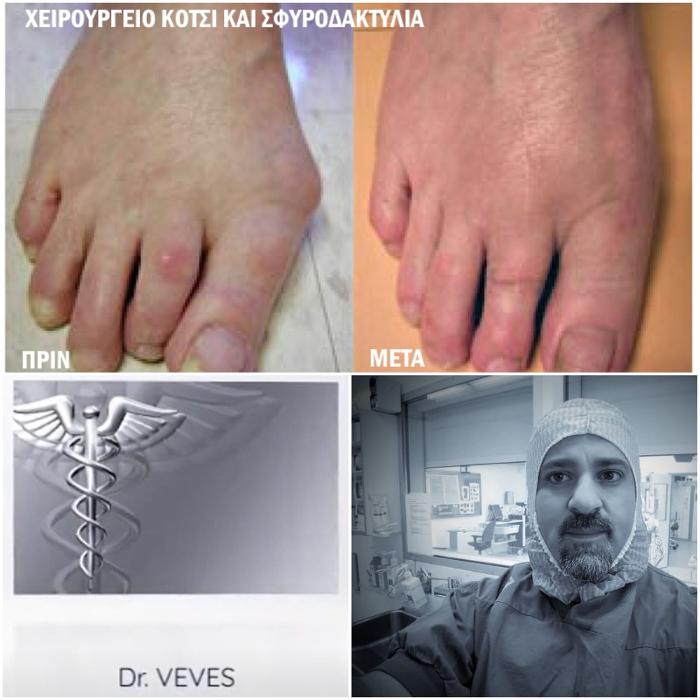

Ορθοπαιδικός Παγκράτι, θεραπεία αρθρίτιδας Παγκράτι, ρήξη μηνίσκου Παγκράτι

ρήξη χιαστού Παγκράτι, ορθοπαιδικό ιατρείο Παγκράτι, ορθοπαιδικός Παγκράτι

Ρήξη μηνίσκου Παγκράτι, ρήξη χιαστού Παγκράτι, ορθοπαιδικό ιατρείο Παγκράτι

Αρθροσκόπηση γόνατος Παγκράτι, Ορθοπαιδικός Παγκράτι, χειρουργός ορθοπαιδικός Παγκράτι, ορθοπαιδικοί ιατροί Παγκράτι, ορθοπαιδικό ιατρείο Παγκράτι

Ρήξη μηνίσκου Παγκράτι, ρήξη χιαστού Παγκράτι, ορθοπαιδικό ιατρείο Παγκράτι